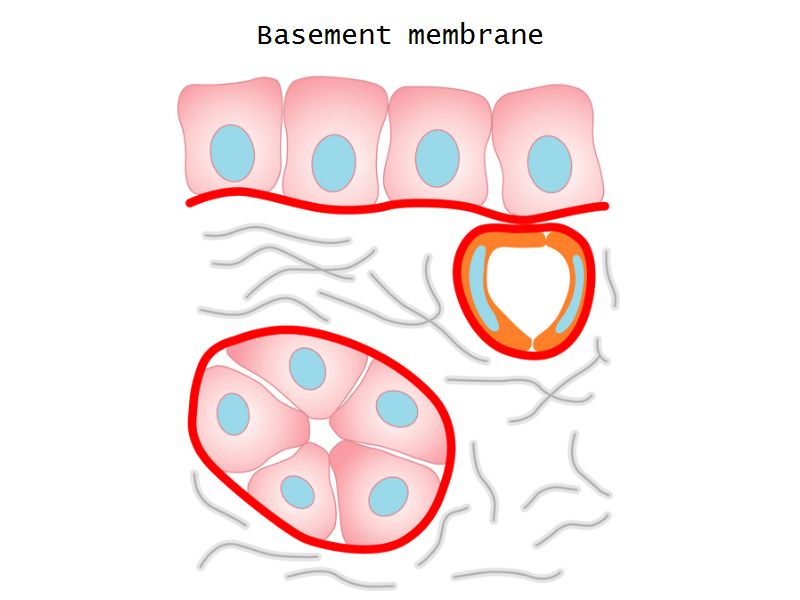

Epithelium layers

- Capillary endothelium

- Visceral layer of epithelium

- Podocytes

- Resting on glomerular basement membrane

- Capsular space

- Parietal layer of epithelium

- Simple squamous epithelium

Glomerular filtration barrier

- Three layers

- Fenestrated epithelium

- Exclude blood cells & platelets

- Glomerular basement membrane

- Main filtration barrier

- Thick

- Fused epithelial & endothelial BM

- Replenished by podocytes due to removal by mesangial cells

- Glomerular epithelium

- Through filtration slit